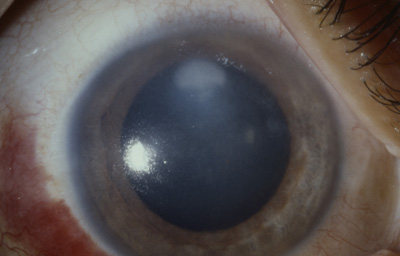

Caso No18.

Paciente masculino de 34 años, agricultor; 20 meses antes de la consulta sufrió picadura en el Ojo Derecho de avispa amarilla “la llaman vaquera” en Saravena. Operado con ltrante a los 4 meses.- Se aplica Optimol

Refracción: AV: PL y PL ( Discrimina rojo y verde) Rx no ayuda por Opacidad

Al examen OD Leucoma denso central con grandes bullas y vaso estromal profundo que penetra a las 6; notable engrosamiento corneal, ( Fistula interna en córnea?) y no panus vascular periférico, midriasis paralítica, goniosinequia en 360o ?.- catarata intumescente, cicatriz quirúrgica superior, Tono digital medio (Foto No 19)

Foto 19 - Leucoma denso con bullas y vaso estromal profundo a las 6

Conducta: Se realiza Queratoplastia penetrante 8.2 mm + Sinequiotomía angular con Viscoelástico + Extracapsular +LIO en OD. En el postoperatorio, injerto trasparente con hipertensión ocular controlada con medicación, gran excavación del Nervio Optico

A los 151 dias de postoperatorio, se aprecia edema del injerto.- Se inició tratamiento; a los 9 meses de postoperatorio se retiraron las suturas, manteniendo el tto antihipertensivo.- EL PACIENTE NO REGRESO